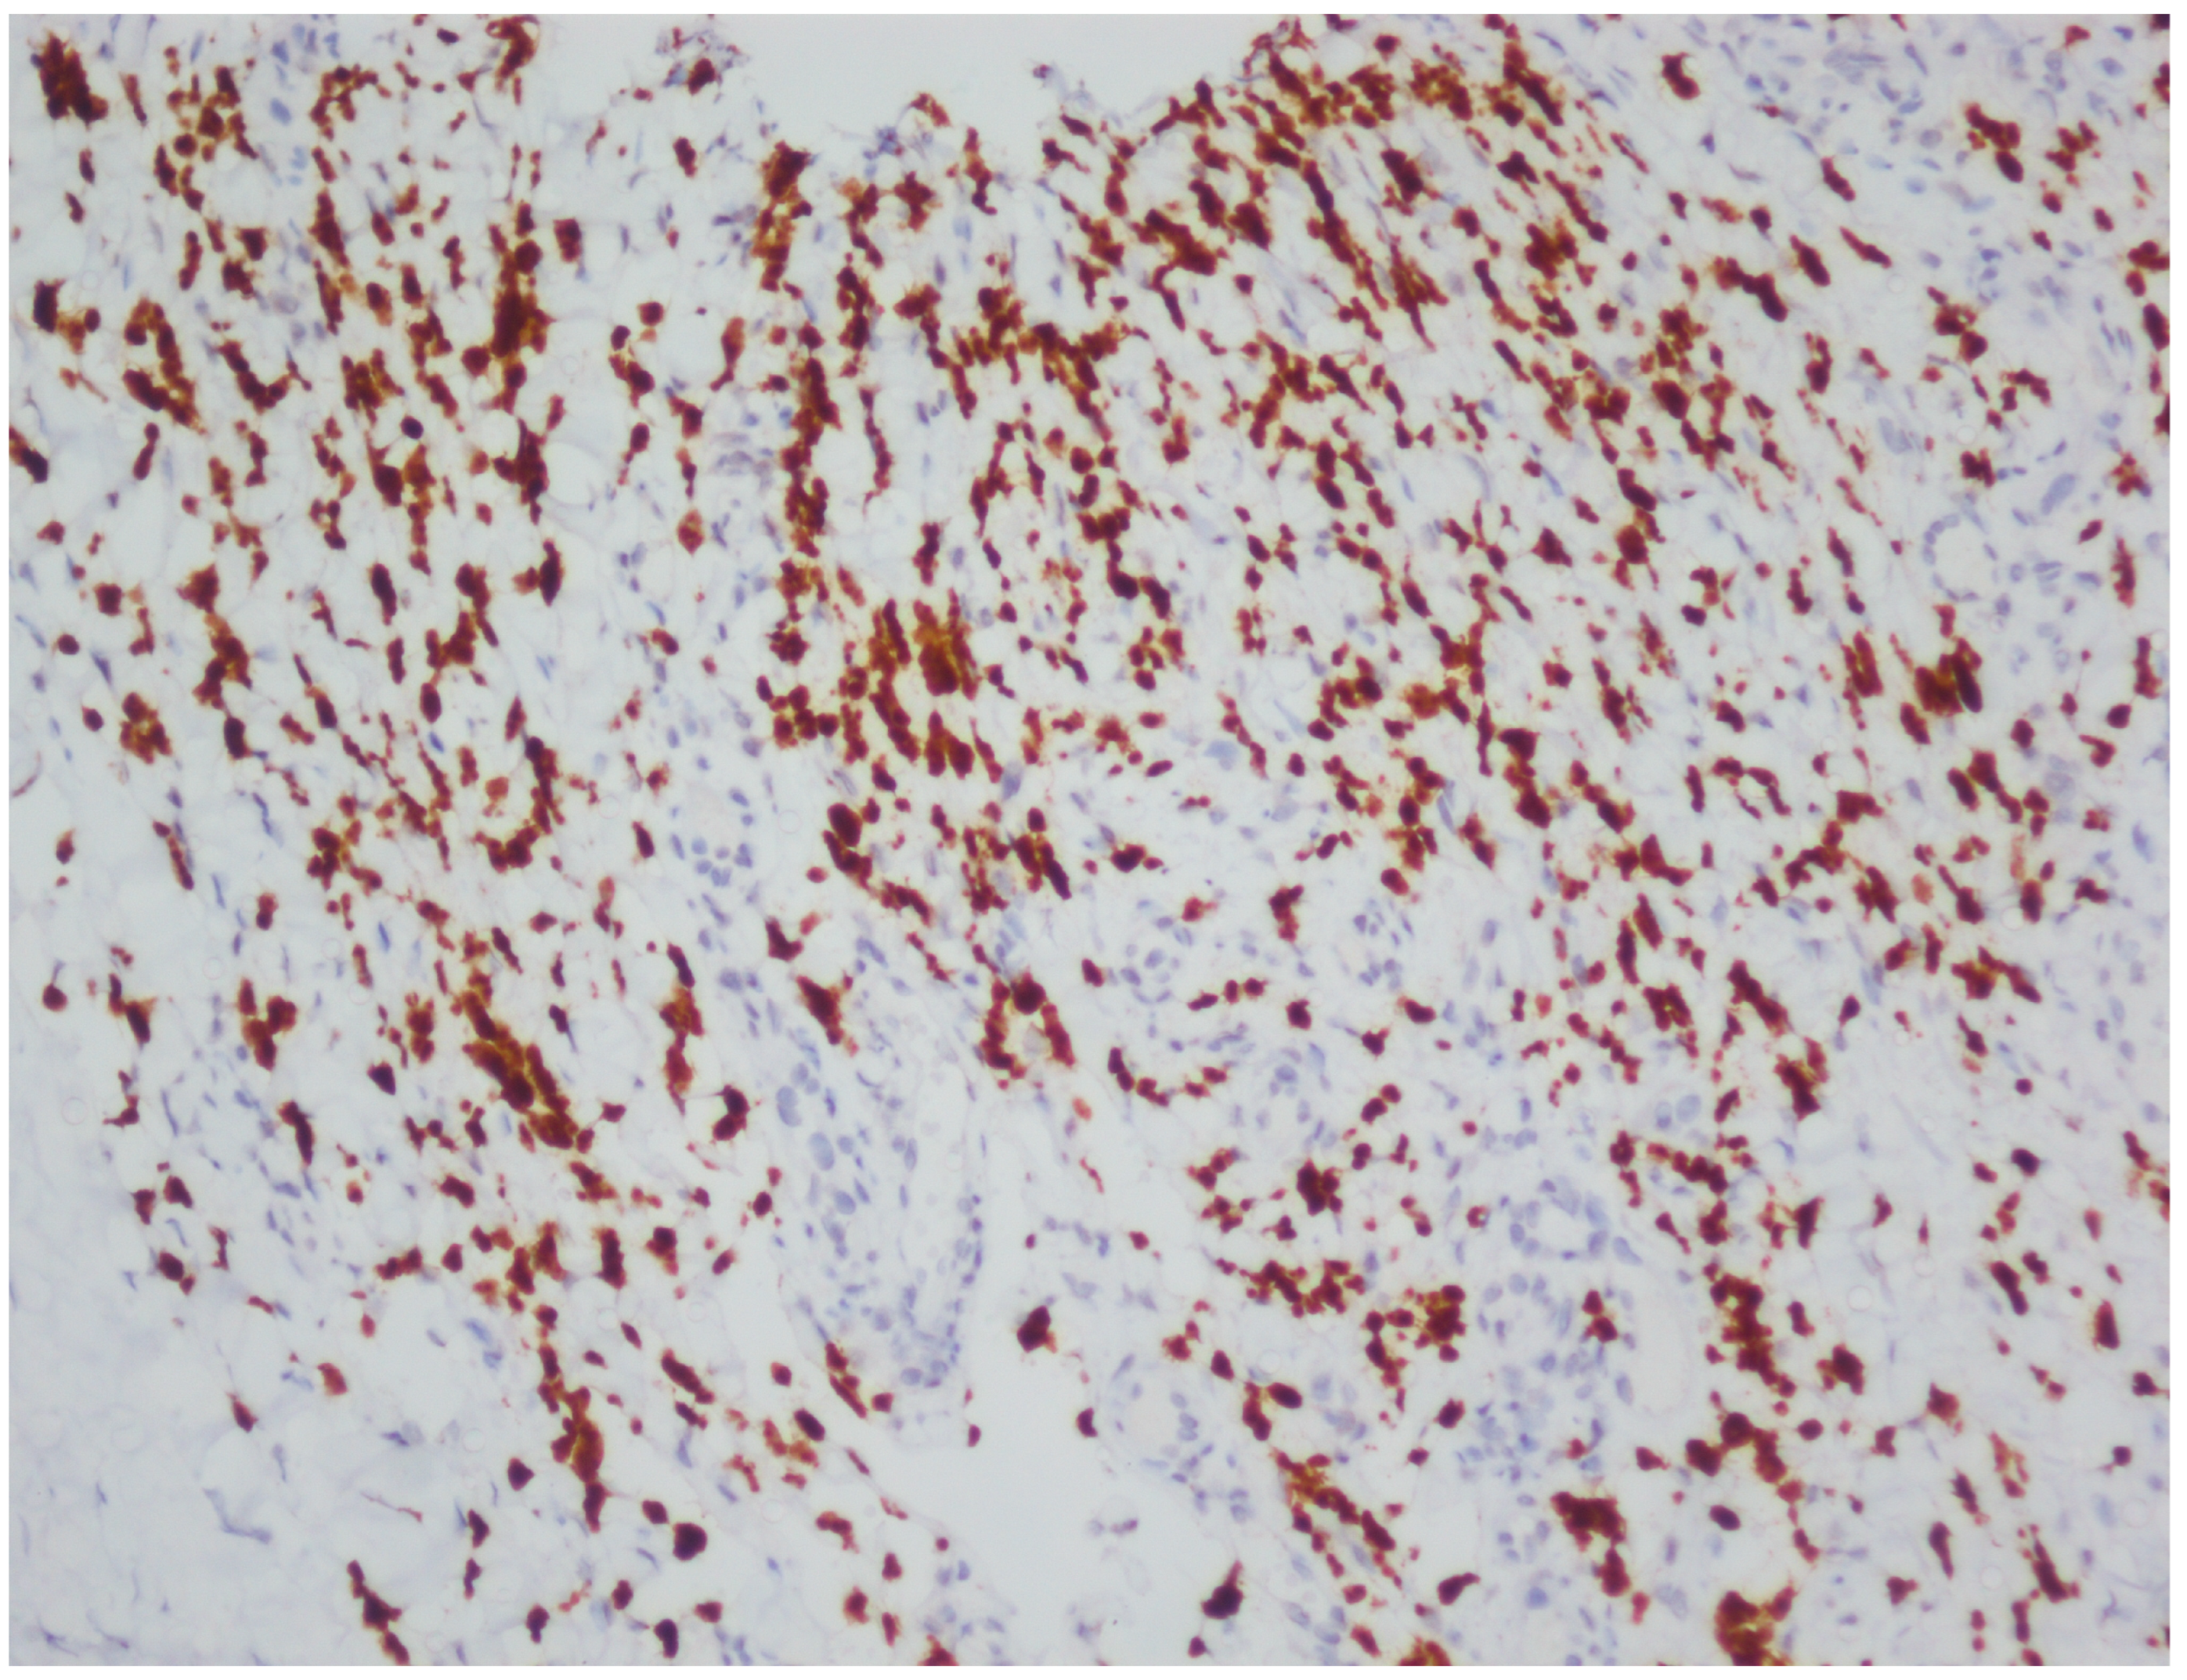

2.5. Histopathological Processing and Immunohistochemistry

| LANA | Latency-associated nuclear antigen |

| DAB | 3,3′-diaminobenzidine |